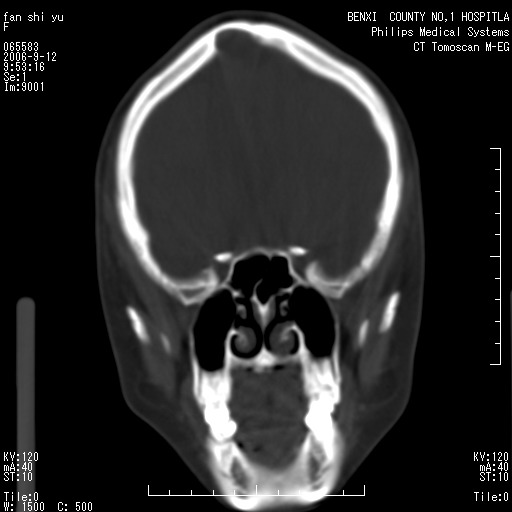

标题: CT4607:看看这个头颅冠状位。

女,22岁,自觉头顶部质硬包块.

考虑蛛网膜粒压迹

巨大蛛网膜粒压迹。

为何没有轴位扫描 考虑蛛网膜囊肿压迹 可mr检查确诊

考虑:蛛网膜囊肿压迹 建议作mri检查确诊